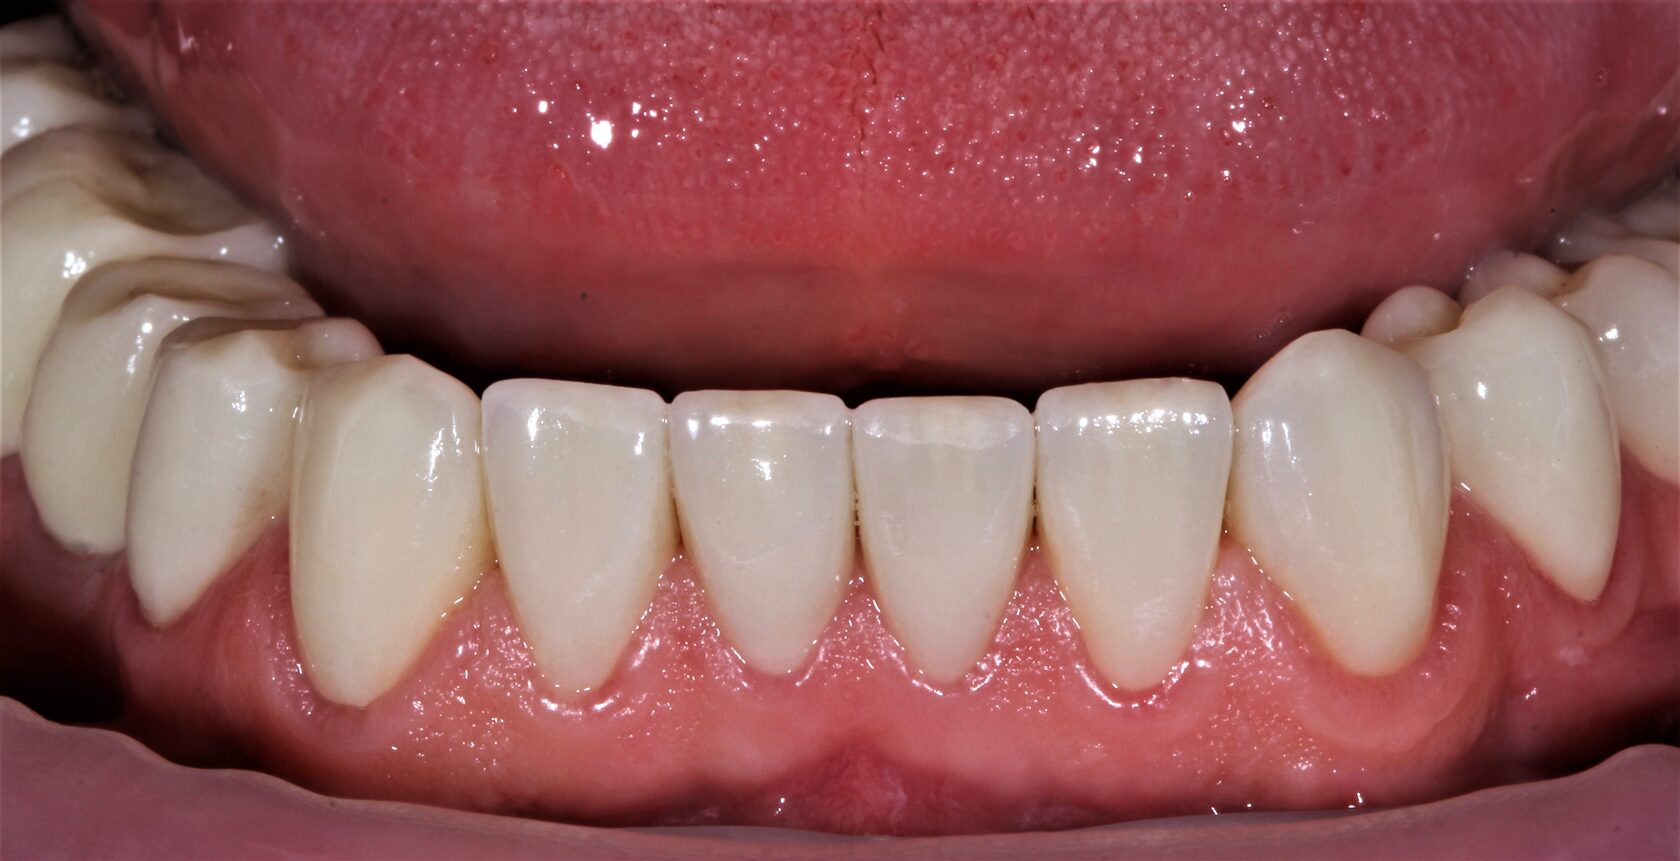

В данном клиническом случае представлена комплексная работа, состоящая из:

3 Сложное функционально-эстетическое протезирование (завышение прикуса на временных

коронках, стабилизация мышечного тонуса и позиции ВНЧС, перевод временных конструкций

в постоянные).

Длительность лечения составила более 1 год.